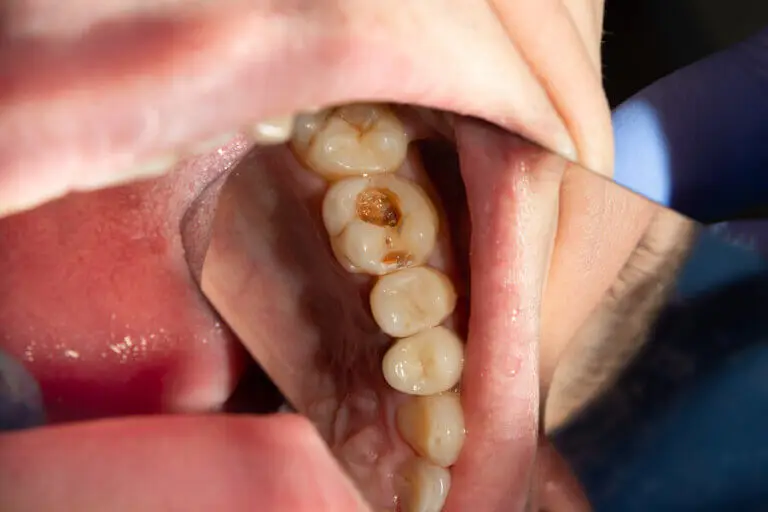

La caries comienza como una mancha blanca, de aspecto tizoso, provocada por una hipocalcificación del esmalte. Si sigue desmineralizándose, la enfermedad progresa y se forma una cavitación de color oscuro.

Durante su evolución es incluso capaz de partir la pieza dental. Una vez que la caries llegue a la dentina, se comienza a presentar sensibilidad al frío, al calor y al dulce. El tratamiento en este momento sería la obturación.